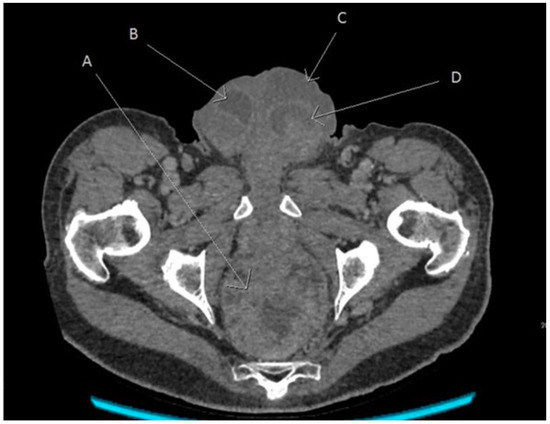

An urgent computed tomography scan was requested, revealing a possible rectal cancer with bilateral hydrocoeles (Figure 1). Urgent debridement of the scrotal tissue for Fournier’s gangrene was undertaken. Rectal biopsies revealed a villous adenoma with a high-grade dysplasia. The scrotal biopsies showed surface ulceration of the skin with a pronounced acute inflammatory infiltrate with abscess formation and infarction in the underlying dermis which extended to involve the subcutaneous tissues and adherent underlying testicular tissue and tracts along the epididymis in keeping with Fournier’s gangrene. Causative organisms were Staphylococcus aureus and Escherichia coli.

Figure 1. Angled axial reconstruction computed tomography image of abdomen and pelvis showing the rectal tumour, scrotal collection, and bilateral hydrocoeles. A—Rectal tumour, B—Right hydrocele, C—Left scrotal collection, and D—Left hydrocele.